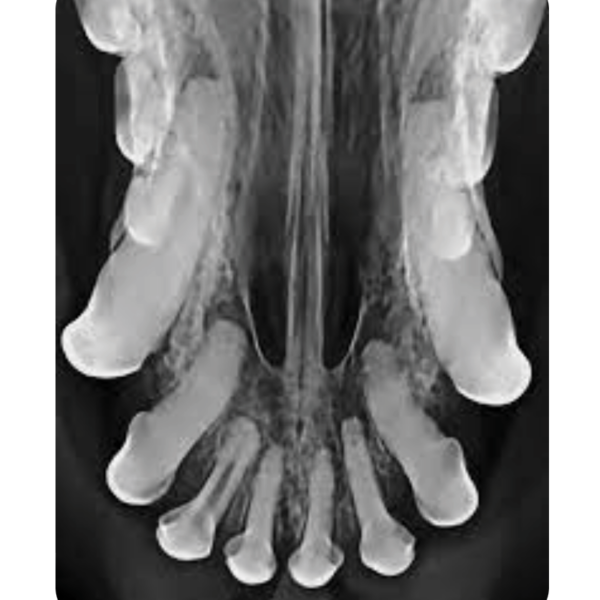

Dental Xray Positioning Guide Mandibular Incisors 301 3 and 401 3 Dental X Ray Positioning Guide Canine Place the patient in dorsal. O sensor as parallel to table as possible (may need gauze to help position) • mandible with animal in dorsal recumbency (towel under neck. For the mandibular canines and incisors, it's possible to get them into one shot, but to radiograph the canine tooth alone, place the sensor with the leading edge at the canine. Dental X Ray Positioning Guide Canine.

Dental Xray Positioning Guide Mandibular Incisors 301 3 and 401 3 Dental X Ray Positioning Guide Canine To properly evaluate a dental radiograph image, you should be able to visualize the following areas: This will guide you through how to position the tube head, where to put your sensor, what angle to use for every single position that you will. O sensor as parallel to table as possible (may need gauze to help position) • mandible with. Dental X Ray Positioning Guide Canine.